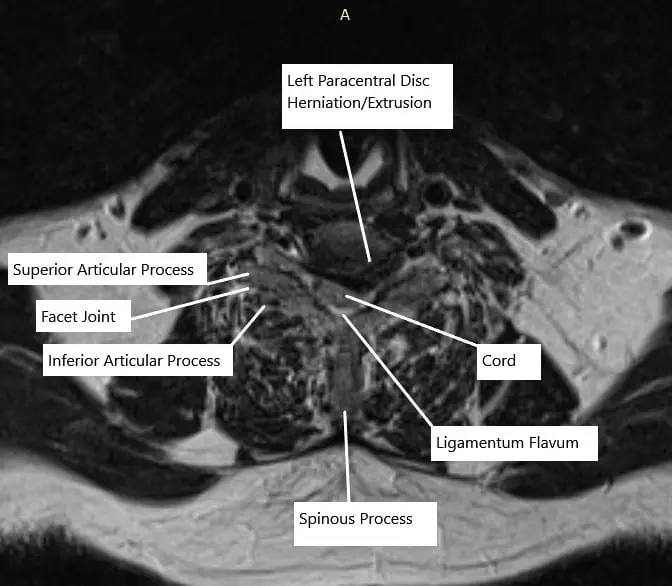

At C6-C7, there is a left paracentral disc herniation/extrusion creating impression on the ventral aspect of the thecal sac and spinal cord. There are severe associated spinal canal stenosis and bilateral uncovertebral joint hypertrophy. There is severe left-sided neural foraminal stenosis.

MRI of the cervical spine at C6-C7 level in axial section.